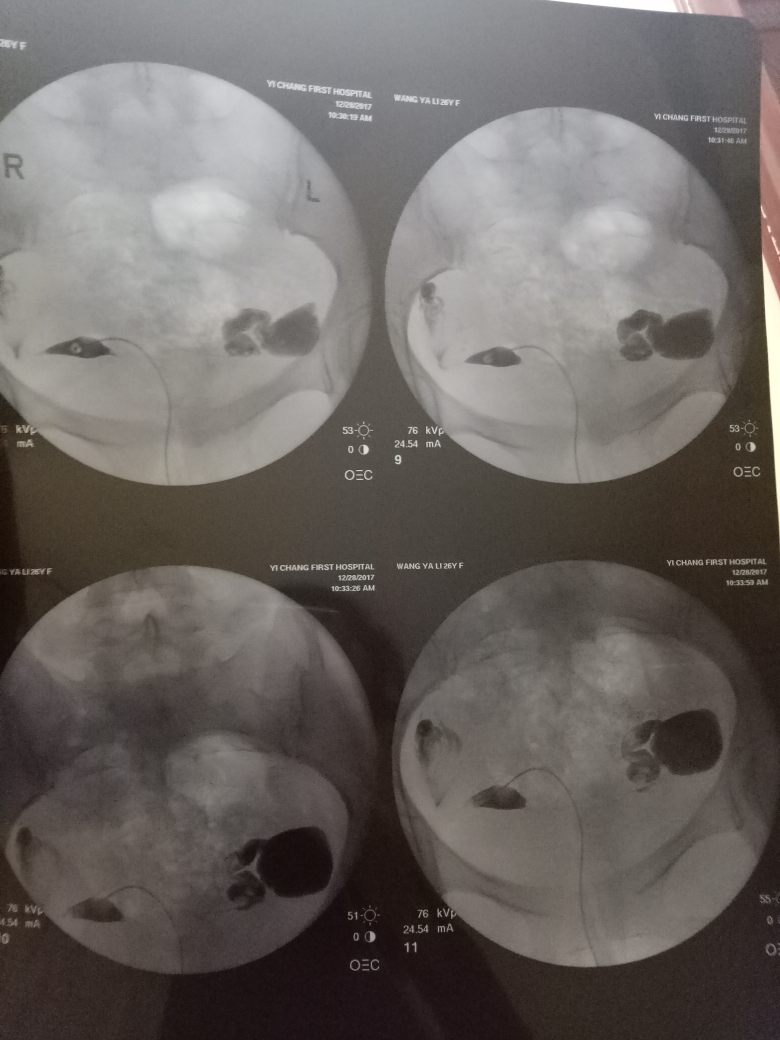

在現(xiàn)代醫(yī)學(xué)中,造影技術(shù)廣泛應(yīng)用于臨床診斷,對于不孕癥的診斷和治療也起到了重要作用,造影是一種通過放射線、超聲波等影像技術(shù)觀察人體內(nèi)部結(jié)構(gòu)和狀況的方法,完成造影后的第二個(gè)月,很多夫婦關(guān)心是否容易懷孕,造影本身并不會直接影響懷孕,但了解身體情況后,有針對性地進(jìn)行治療和調(diào)理,確實(shí)有助于提高懷孕的幾率。

通過造影技術(shù),醫(yī)生可以清晰地觀察到子宮內(nèi)部環(huán)境,如子宮內(nèi)膜厚度、輸卵管通暢情況等,若子宮環(huán)境良好,第二個(gè)月懷孕的機(jī)會將大大增加。

造影技術(shù)還可以評估卵巢功能,如卵泡數(shù)量、質(zhì)量等,若卵巢功能正常,有助于排卵和激素分泌,從而提高懷孕幾率。